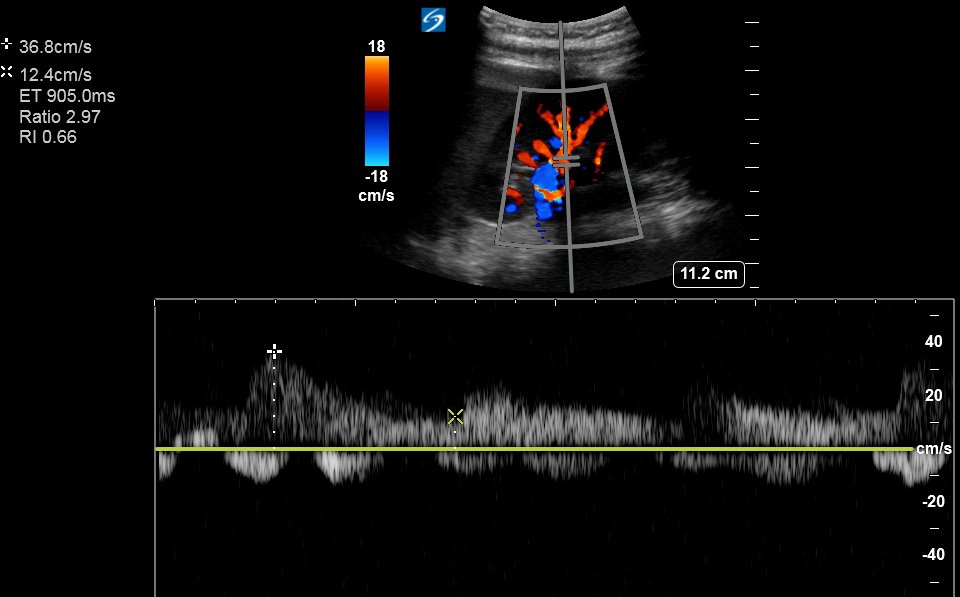

Doppler ultrasound for venous congestion - #VEXUS - has truly been game-changing in my clinical #POCUS practice.

Here's the TL;DR on the concept of #VEXUS - 🧡

For a long time, physicians were focused solely on forward flow; we lacked an appreciation of the harms of right-sided venous congestion, as well as a means to assess it at the bedside.

We are now increasingly recognizing the harms of venous congestion, and realizing the importance of the fluid tolerance and #ThePeoplesVentricleImage When assessing for clinically significant organ congestion with ultrasound, basic 2D ultrasound has its limits.

A plethoric IVC is a great start - it is highly sensitive, but not specific, for organ-level congestion. A high CVP is a prerequisite to organ congestion; but by itself is not enough!

Enter: #VEXUSImage